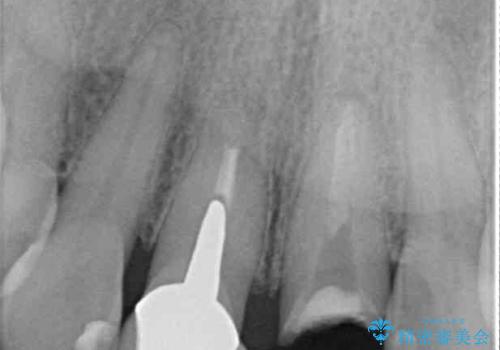

根管治療後に痛みは軽減しましたが、僅かな痛みが続くとのことで、レントゲン写真では病変は認められなかったものの、歯根端切除を行うこととしました。処置後は痛みは全くなくなり、安心して補綴治療を行うことができました。